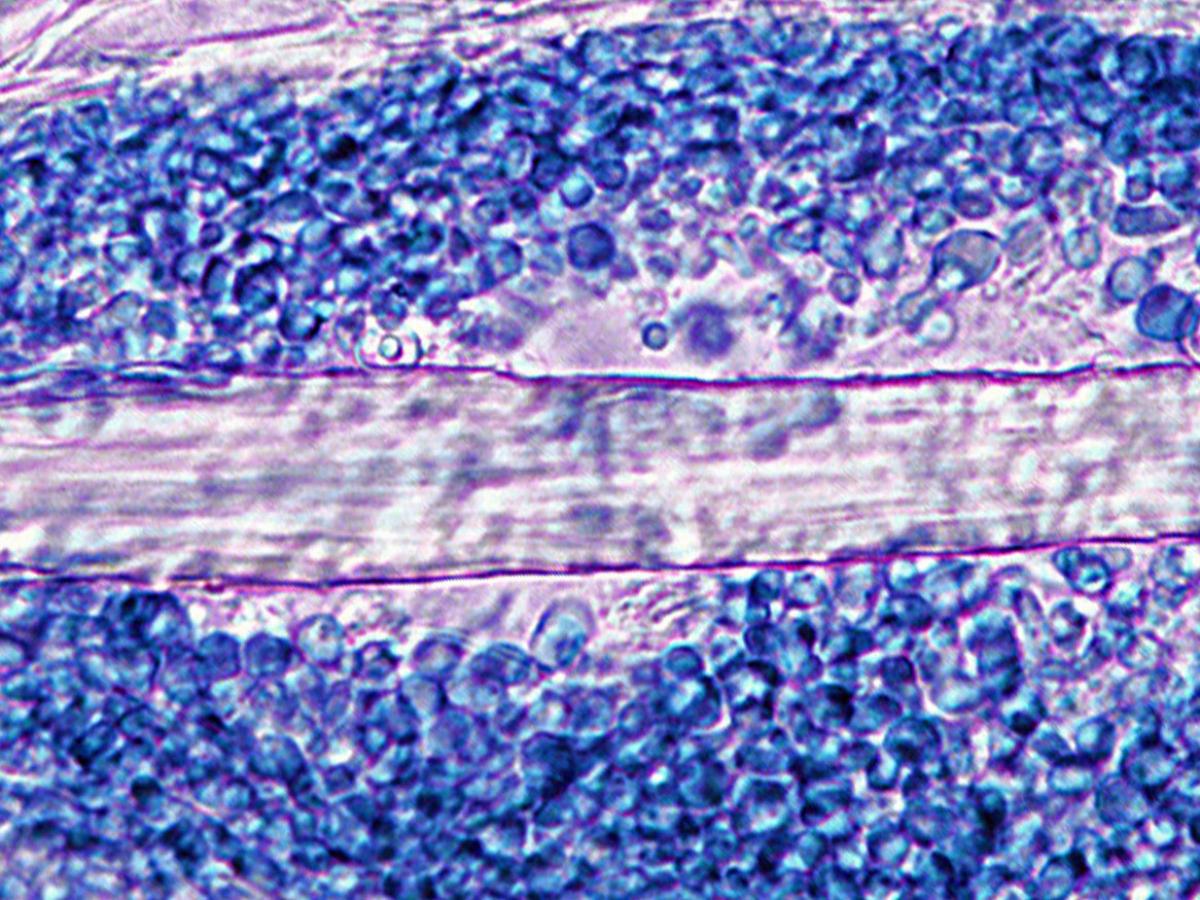

Direct microscopy: KOH mount of infected hairs showing a large spored ectothrix invasion typically caused by N. gypsea.

Microscopy: Cultures produce abundant, symmetrical, ellipsoidal, thin-walled, verrucose, 4-6 celled macroconidia. The terminal or distal ends of most macroconidia are slightly rounded, while the proximal ends (point of attachment to hyphae) are truncate. Numerous clavate shaped microconidia are also present, but these are not diagnostic.